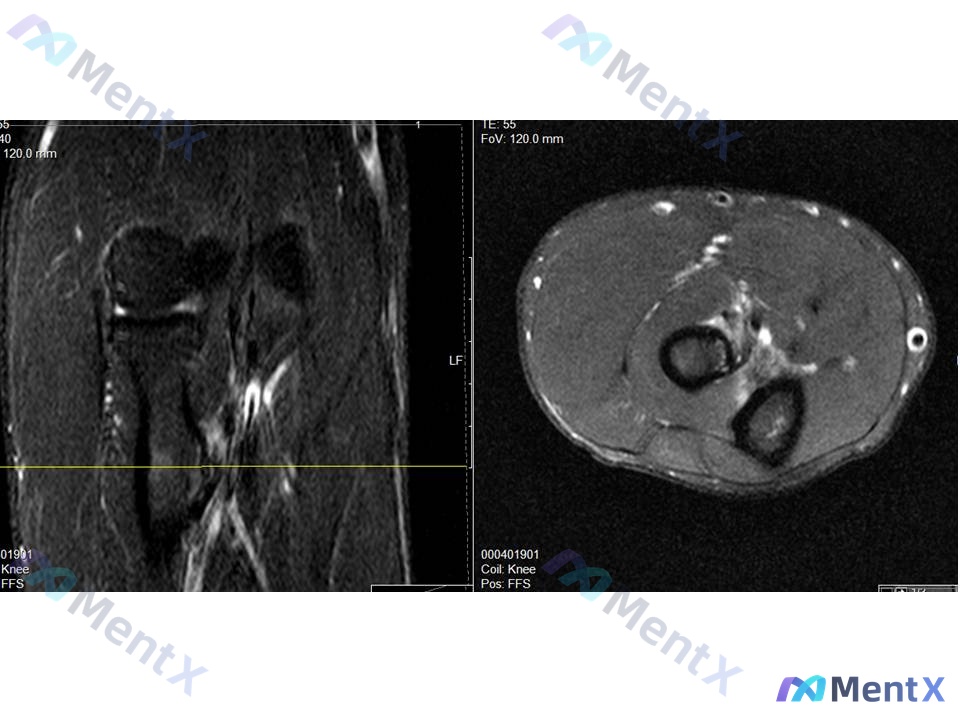

这里有个小插曲:原始报告里居然把右肘MRI误判成了膝盖MRI…

- 右肘MRI(修正后聚焦):虽然报告张冠李戴,但结合临床,应该重点看肱二头肌腱止点(桡骨粗隆)——预期会有肌腱增粗、T2/PD压脂高信号(水肿/炎症)、纤维部分中断的表现。